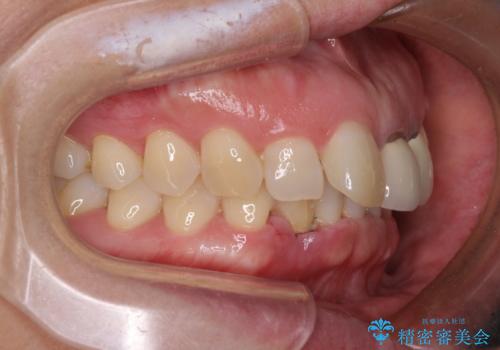

- 下顎前歯が抜けそうとのことで来院された患者様です。

初診の状態ではすぐにでも抜けそうな状態で、インプラントによる補綴治療を行うこととしました。

インプラント治療に際し、前歯の叢生に対する矯正治療を提案したところ、興味を持たれたので、インビザライン・ライトによる矯正治療を行うこととしました。

抜歯後にスペースができると恥ずかしいため、抜歯した歯を接着剤で固定した上で矯正治療を行い、その後インプラントやオールセラミッククラウンの装着を行うこととしました。